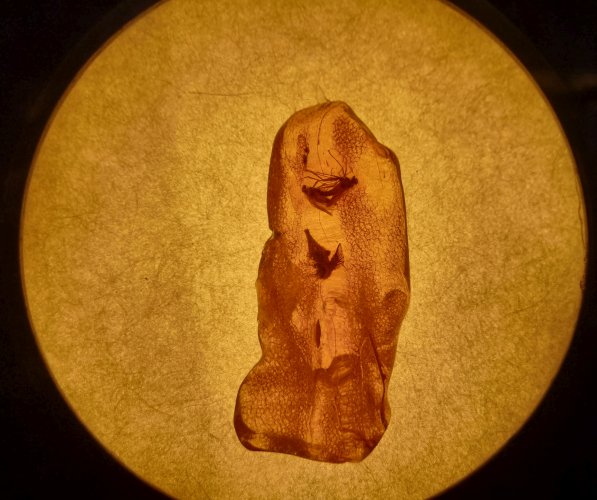

Baltictour-6-64.jpg

64 | Baltictour-6-64